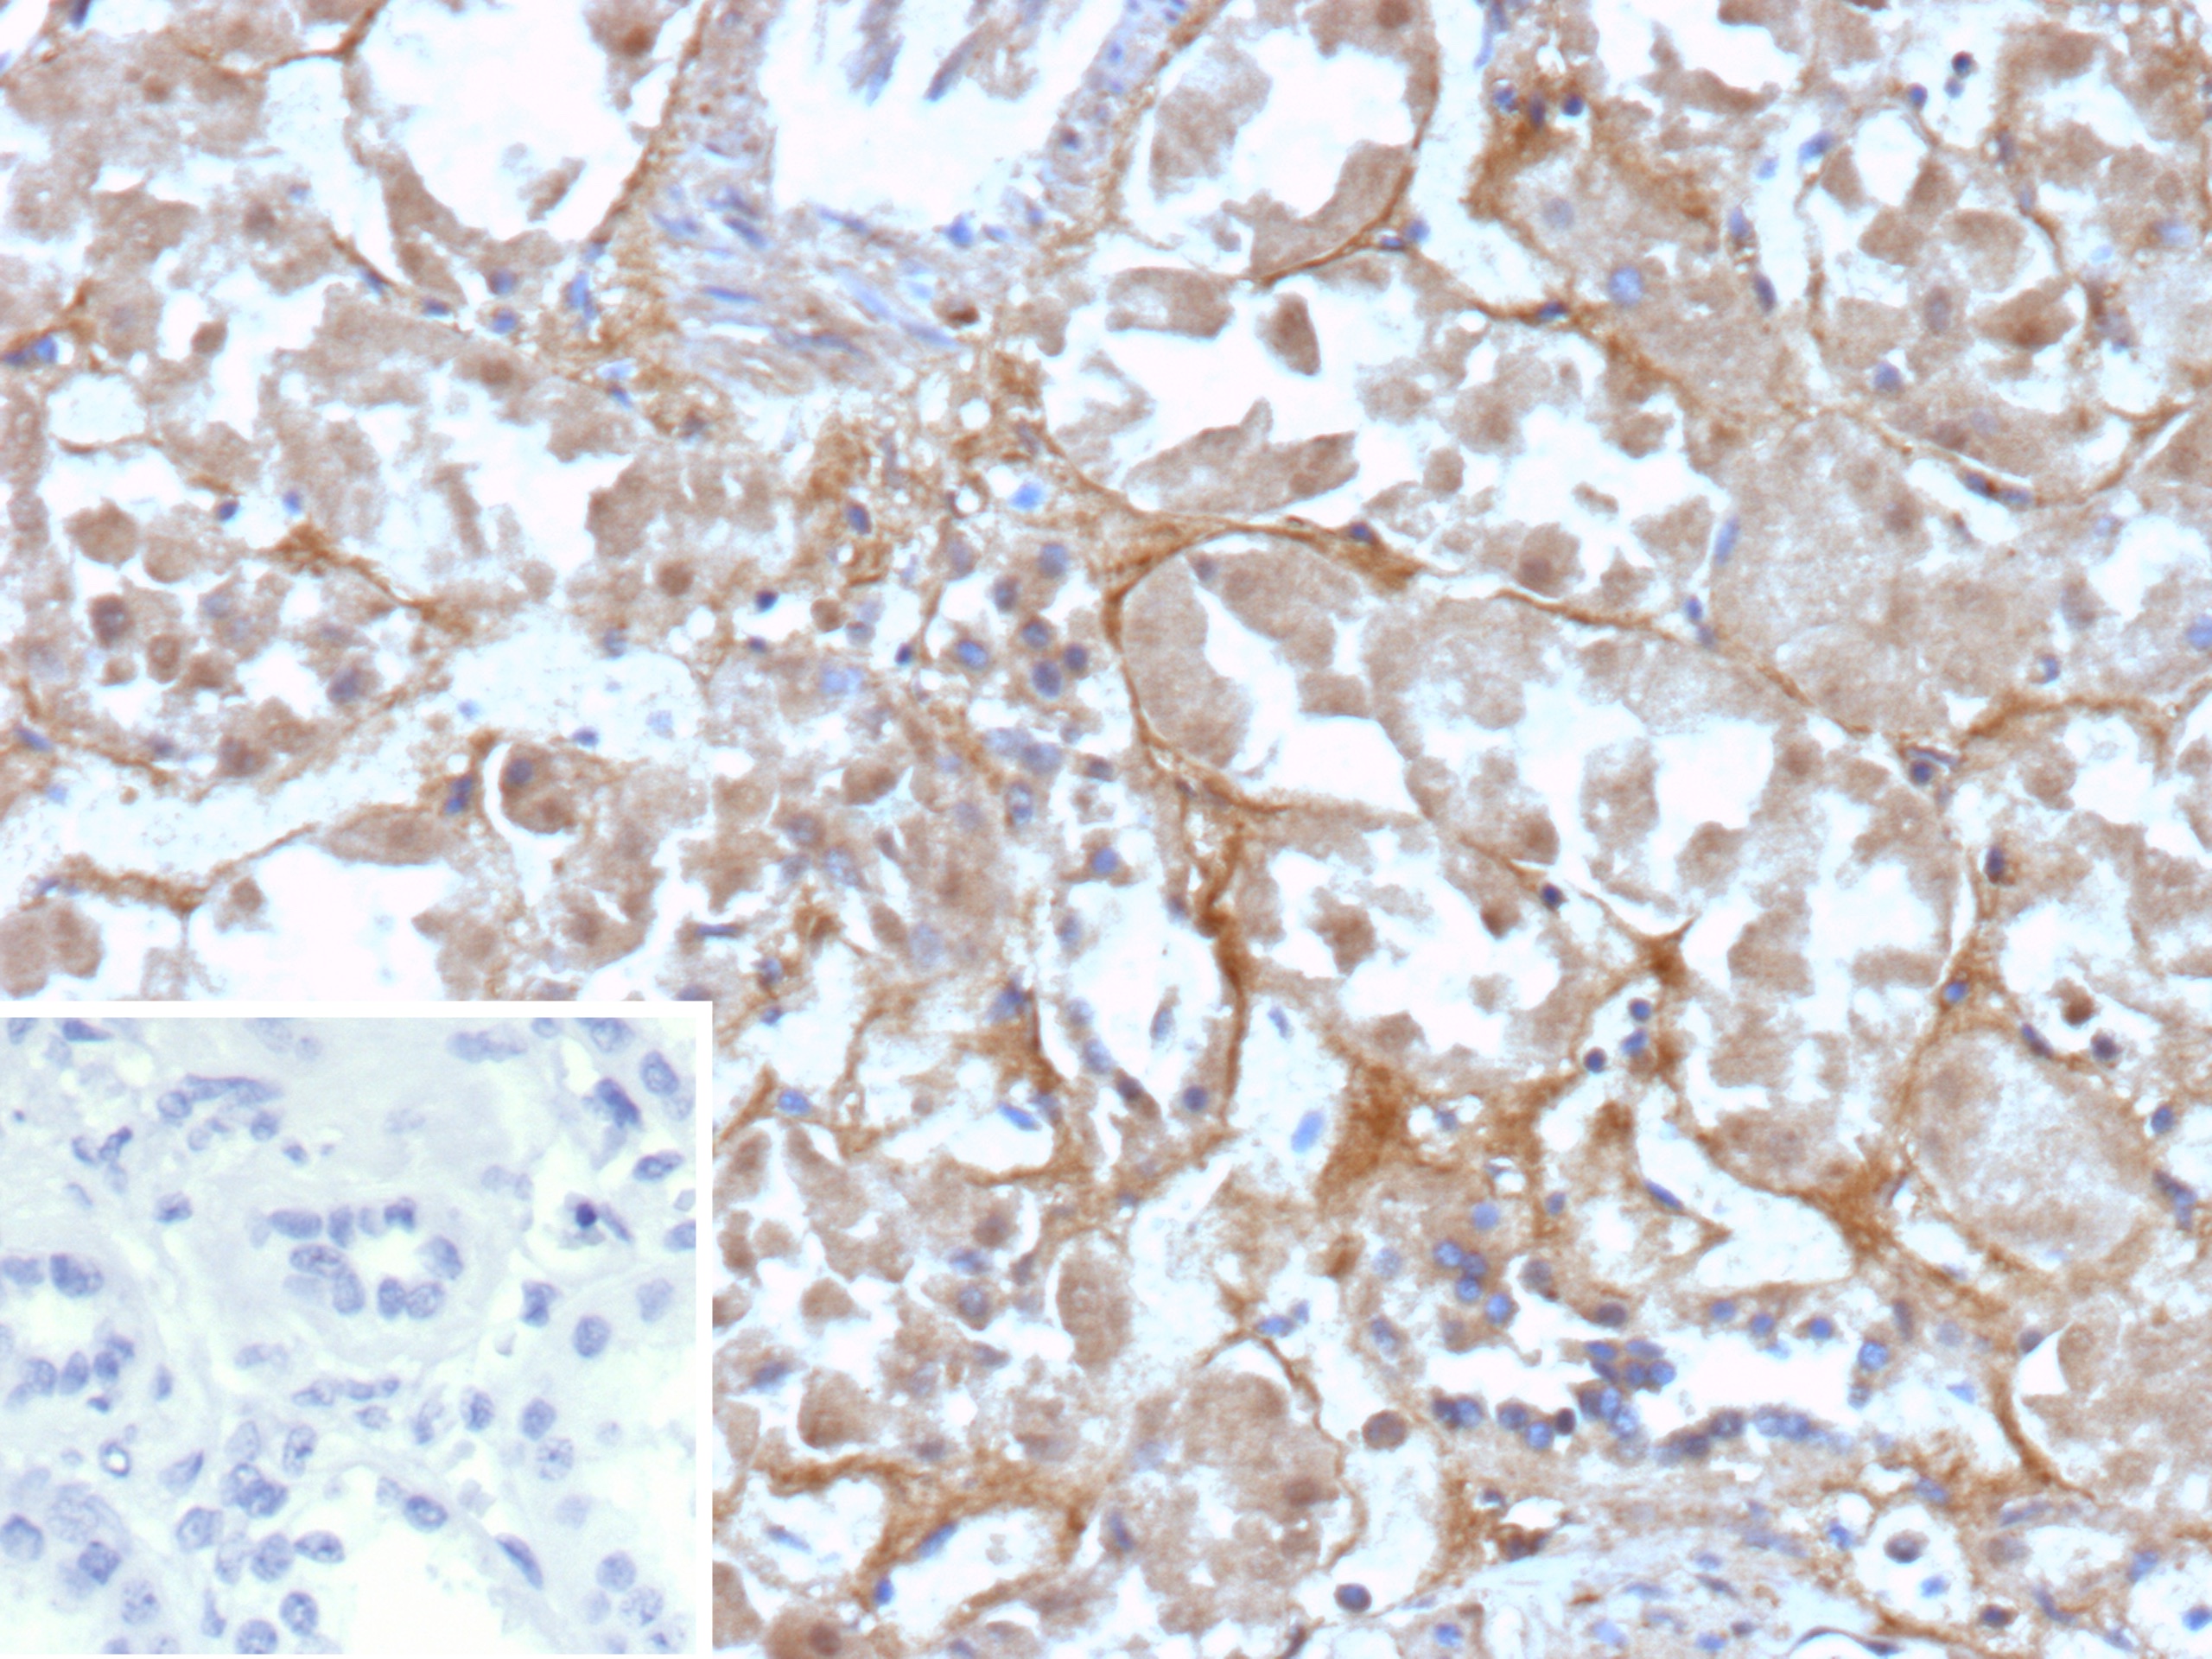

Formalin-fixed, paraffin-embedded human renal cell carcinoma stained with CD200R1 Recombinant Rabbit Monoclonal Antibody (CD200R1/9919R). Inset: PBS instead of primary antibody; secondary only negative control.